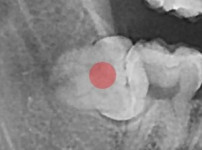

完全埋伏智齿